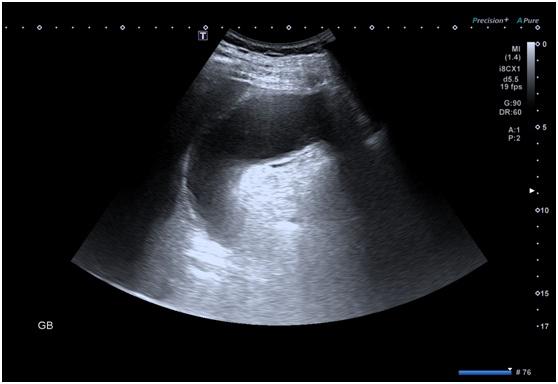

入院后完善相关检查 , 腹部超声及CT发现王老伯的胆囊增大、胆囊壁明显增厚 , 考虑急性胆囊炎并伴有胆道感染 , 由于胆囊张力过高并不适宜立即手术治疗 。 随着症状不断加重 , 为了避免病情进展过快引起胆囊坏疽而对王老伯的身体健康和生命安全造成危害 , 外科医生迅速联系超声科医生为其进行超声引导下胆囊置管引流术 。

穿刺前肿大的胆囊图示